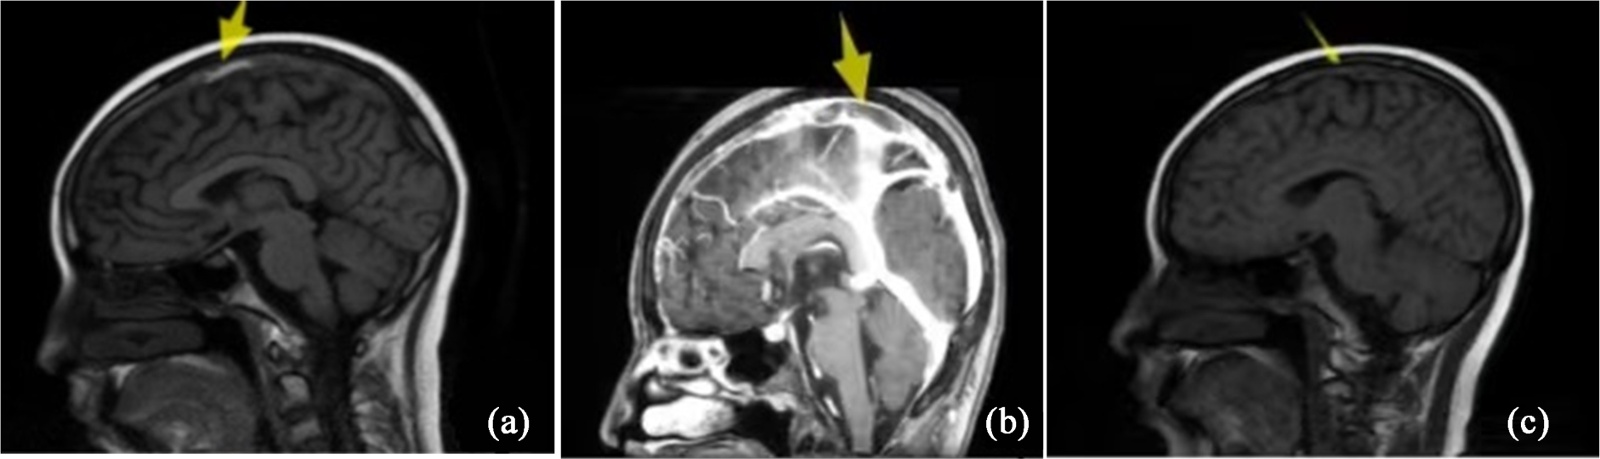

患者,女,12岁,因“咳嗽10天伴活动后呼吸困难”入院。依据骨髓MICM结果诊为急性淋巴细胞白血病(T系,中危)。入院颅脑MR未见异常,按CCCG-ALL-2020方案予VDLD诱导缓解治疗。治疗期间多次查血凝常规示FIB最低0.74 g/L (正常值范围2.38~4.98 g/L),AT-III最低71% (正常值范围83%~128%),输注人纤维蛋白原2次。治疗第33天,患儿出现反复全身性抽搐3次,颅脑CT平扫、电解质、血常规未见异常。血凝常规:PT 13.7 s (正常值范围9.4~12.5 s),APTT 35.7 s (正常值范围25.1~38.4 s),FIB 1.09 g/L,AT-III 73%,DD 390 ng/mL (正常范围0~500 ng/mL)。颅脑MR:右额叶、右枕部皮层见斑片状长T1长T2信号影,FLAIR高信号影(如图1(a))。脑CT静脉血管成像(CTV):上矢状窦、直窦管腔内见条状、斑片状充盈缺损(如图1(b))。上肢血管彩超:右上肢贵要静脉段管周血栓形成。予低分子肝素治疗35天,复查脑MR好转,改为利伐沙班序贯治疗。后期再次应用培门冬酶(PEG-Asp),未再有血栓形成,抗凝治疗3月复查颅脑MR示上矢状窦信号轻度不均匀升高、较前减轻(如图1(c)),抗凝治疗期间动态监测血凝正常。

(a) 治疗前脑MR;(b) 治疗前脑CTV;(c) 治疗3月后脑MR。

Figure 1. Comparative cranial imaging of case 1: Pre-treatment vs post-treatment

1. 病例1治疗前后颅脑影像变化